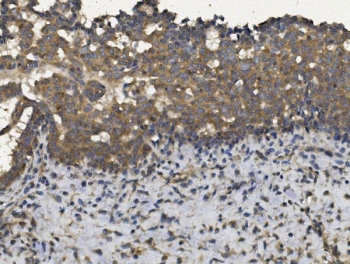

IHC staining of FFPE human breast cancer with EIF2AK4 antibody. HIER: boil tissue sections in pH8 EDTA for 20 min and allow to cool before testing.